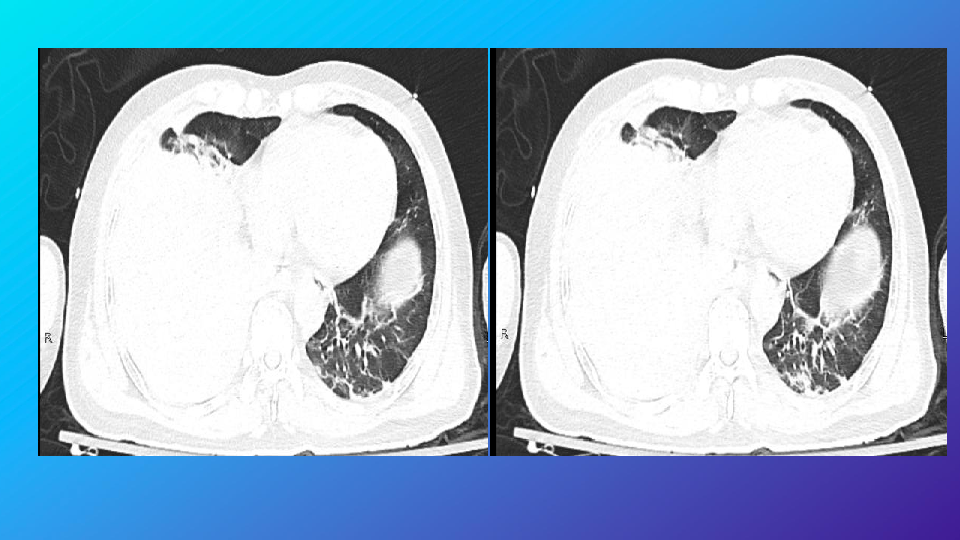

胸部外伤